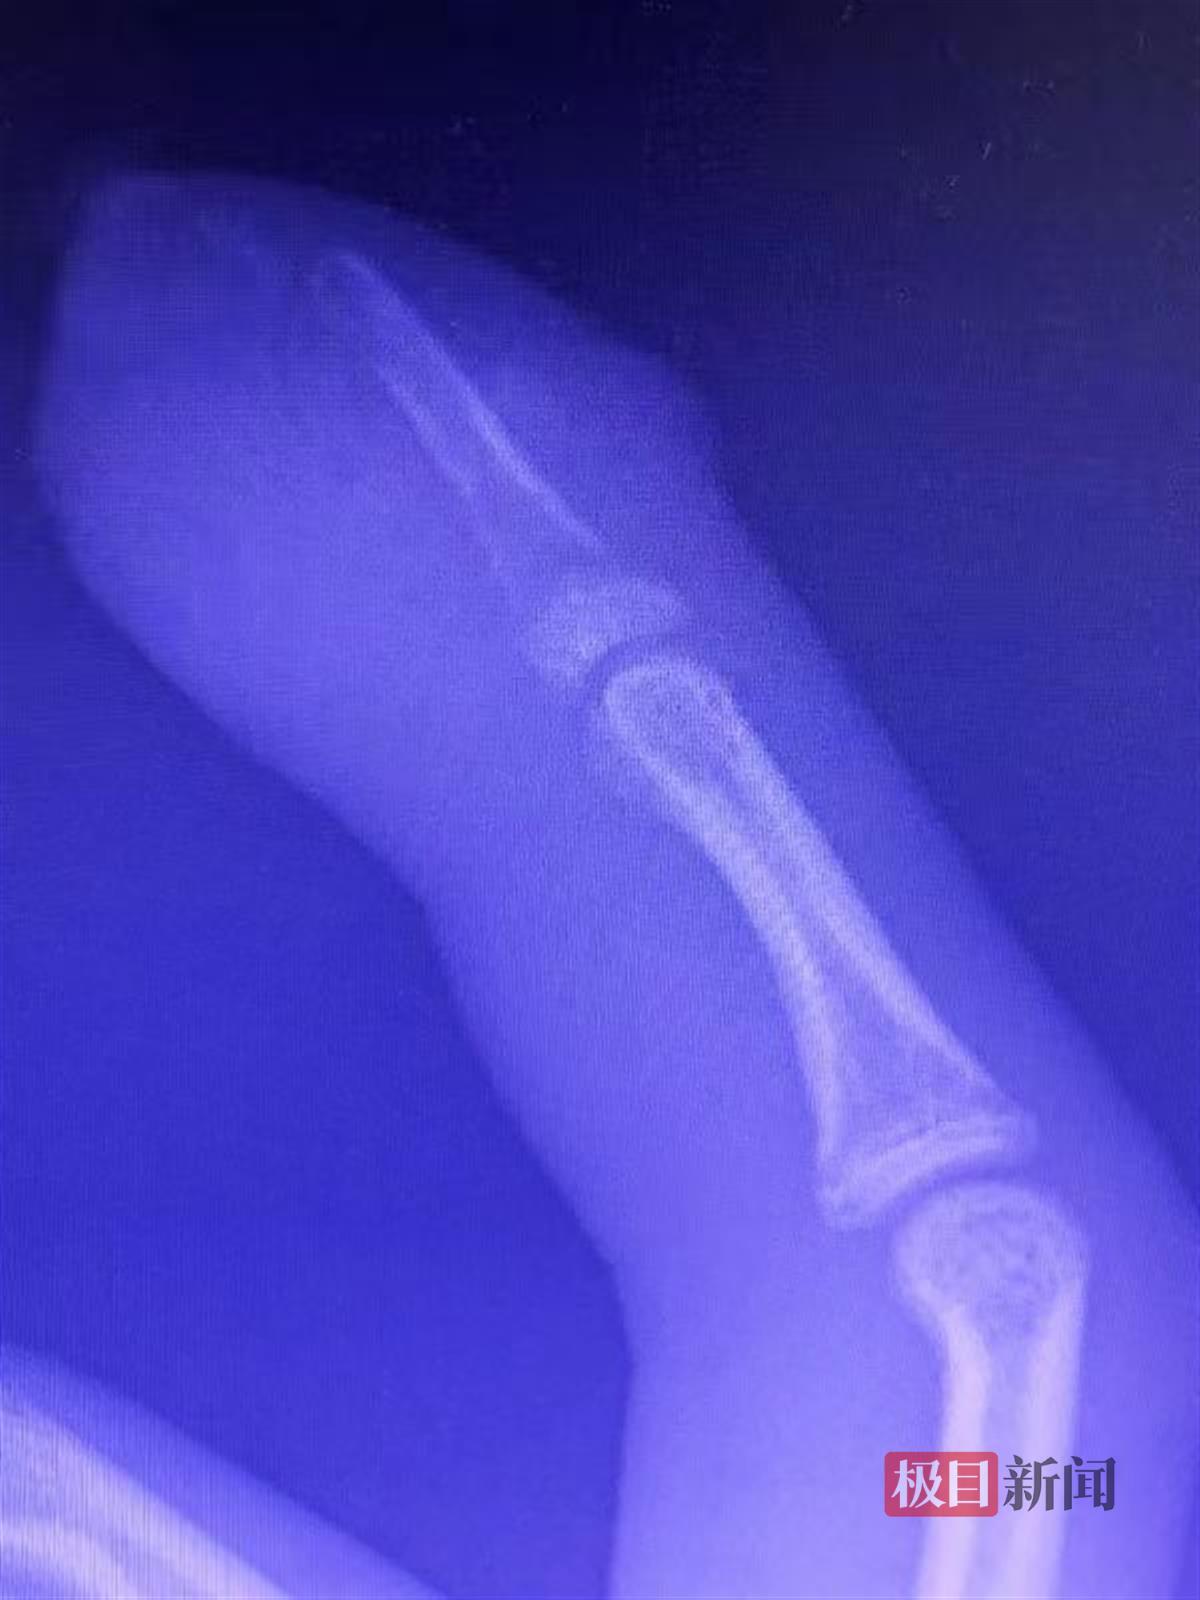

结合X线片检查结果,李涛教授发现小宇不但皮肤有化脓感染,指骨也出现了严重感染,并有明显的骨破坏,骨质像是被“虫子”咬蚀过一样。结合全身高热和局部明显疼痛症状,李涛教授判断他患的是急性骨髓炎。

(图片由李涛教授提供)